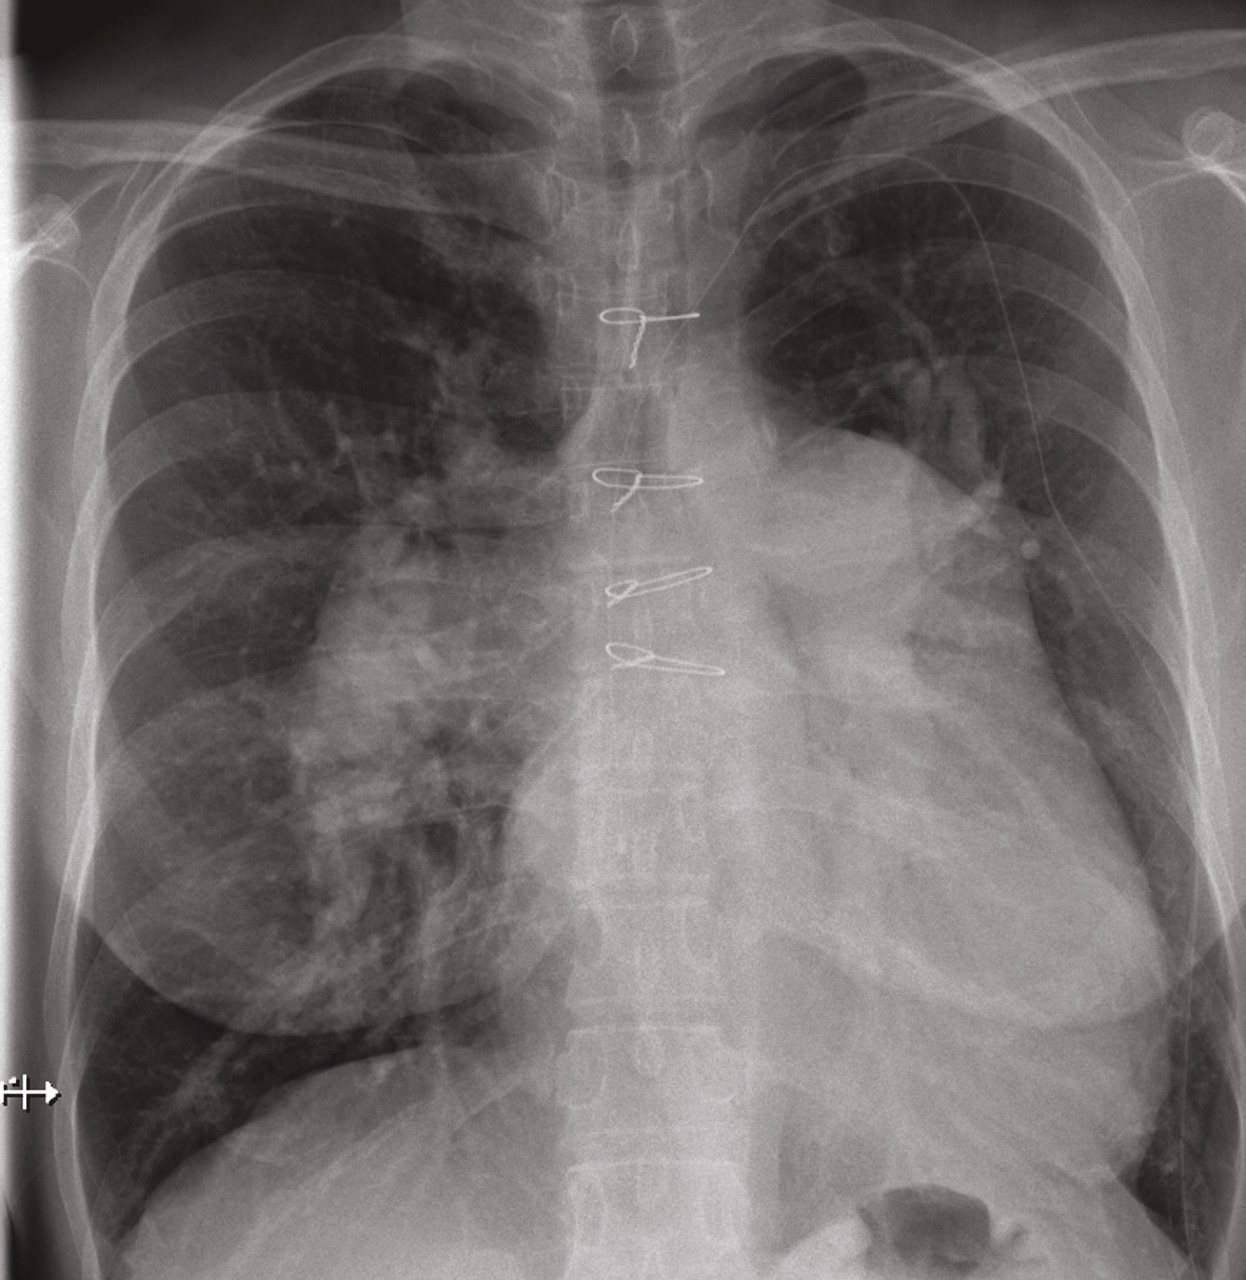

Les marqueurs cardiaques tels que le BNP (Brain natriuretic peptide) et/ou le NT-proBNP (N-terminal pro-brain natriuretic peptide) peuvent être augmentés en cas d’HTP. Ces biomarqueurs sanguins sont également utilisés dans le cadre du suivi des patients atteints d’HTP, une fois le diagnostic confirmé.Radiographie thoracique

La radiographie thoracique montre généralement une dilatation des artères pulmonaires proximales et un élargissement des cavités cardiaques droites (oreillette et ventricule droit) [Épreuves fonctionnelles respiratoires